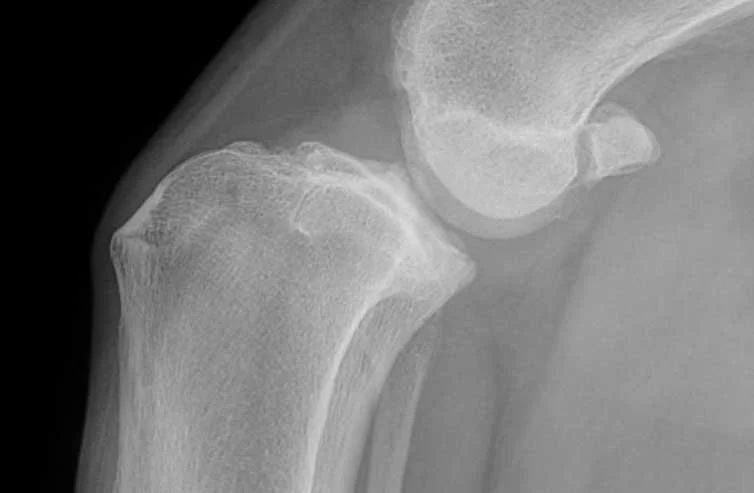

Cruciate ligament disease or injury

Cruciate ligament disease refers to damage or rupture of the cranial cruciate ligament within the knee (stifle) joint. This ligament plays a key role in stabilising the joint during movement. In the Cane Corso, cruciate injury may occur as a sudden traumatic event or develop gradually due to ligament degeneration. Left unmanaged, it can lead to pain, instability, and progressive arthritis.